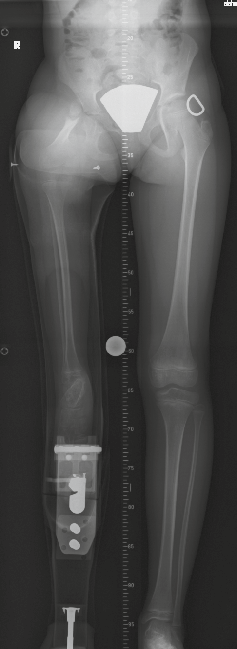

Prothesenversorgung bei Fehlbildung des Femurs

Eine Prothesenversorgung bei Fehlbildung des Femurs kann ohne Gelenk erfolgen, bis die Prothesenlänge das Sitzen unmöglich macht (z. B. im Auto). Dies ist meistens bei Kindern um das 6. Lebensjahr der Fall. Dann ist das Einsetzen eines Prothesenkniegelenks zwingend. Dazu sind marktübliche Produkte jedoch ungeeignet. Um die Überlänge zu reduzieren, haben wir uns entschieden, das Knie hinter dem Fuß des Patienten zu platzieren (Abb. 1 u. 2). Dafür lassen sich allerdings Knie mit ventralem Feststellzug nicht verwenden; vielfach sind die auf dem Markt existierenden Knie zu voluminös. Außerdem ergeben Kniepassteile ohne pneumatische oder hydraulische Steuerung kein befriedigendes Gangbild. Aus diesem Grund haben wir eine Lösung gesucht, um ein passendes Gelenk mit Sperre herzustellen.

Für den Aufbau wird die Prothese steif anprobiert. Das Gelenk wird auf Schaft und Balsaholzteil befestigt; dabei muss auf die Stellung geachtet werden, so dass die sitzende Position ermöglicht wird. Erst dann sägen wir die Prothese auf Zehenhöhe ab (damit diese in sitzender Position ebenfalls frei liegen). Somit erreichen wir eine minimale Länge des proximalen Segmentes (Abb. 4 u. 5). Sobald die Größe des Kindes es zulässt, wird unser selbst entwickeltes Knie durch ein hydraulisches Einachs-Kniegelenk ersetzt. Das erzielte Resultat im Erwachsenenalter spricht gegen eine Amputation des Kinderfußes.